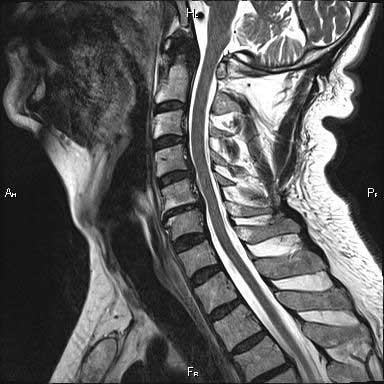

КТ позвоночника применяется для диагностики различных состояний, включая:

- Межпозвонковую грыжу;

- Компрессионные переломы позвоночника при остеопорозе;

- Артриты;

- Сужение спинномозгового канала;

- Опухоли позвоночного столба.

Компьютерная томография поясничного отдела позвоночника может помочь в выявлении кровоизлияний в спинной мозг, нестабильности позвонков и разрастания остеофитов.